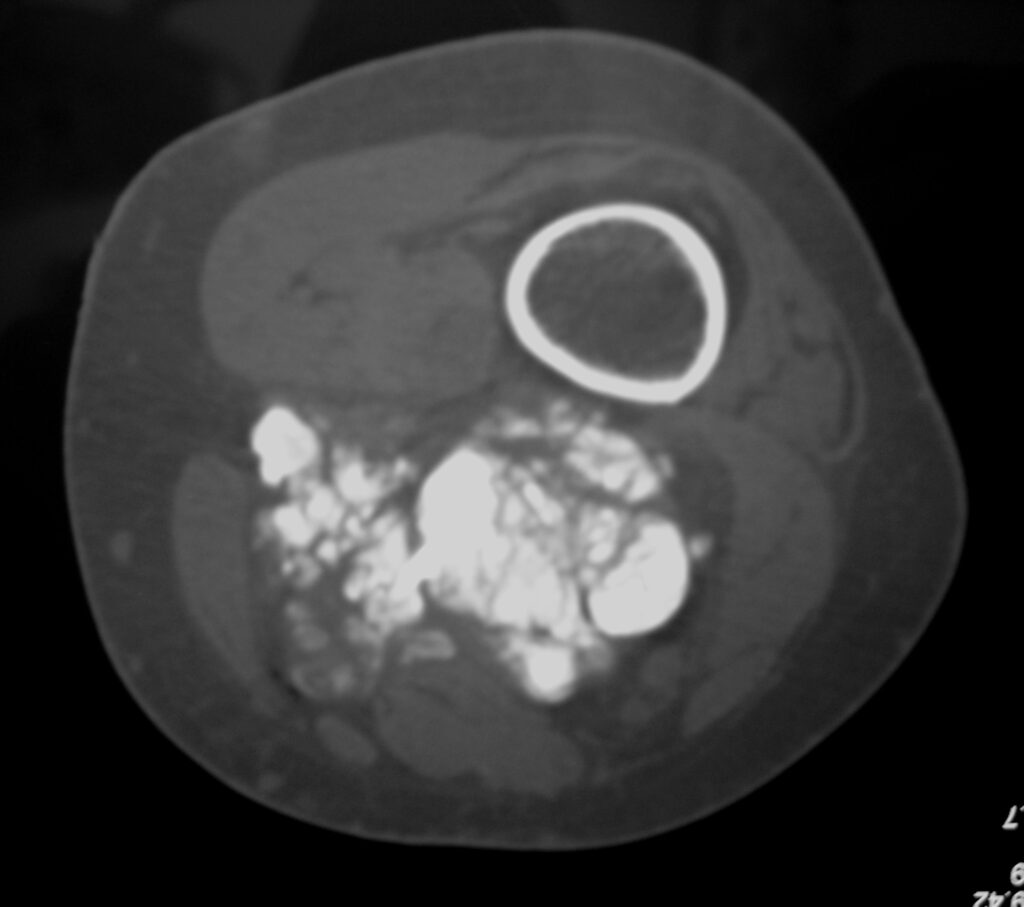

On radiographs, extraskeletal osteosarcomas show a mass with soft tissue density and variable amounts of mineralization best visualize on an Xray or CT scan, which may appear as a dense, cloudlike area (Fig. 1-3). A well circumscribe heterogeneous mass, Isointense to muscle on T1-weighted images and isointense to mildly hyperintense on T2-weighted images (Fig. 4-7). Mineralized areas will be dark on T1 and T2 weighted images.

Fig. 1 & 2: Plain x-rays of the distal femur showing an extraskeletal osteosarcoma. AP (Fig. 1) and Lateral (Fig. 2) views show a soft tissue density with intense mineralization in the posterior thigh. Mass is not originating from the bone.